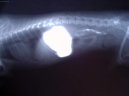

| Léčba interních onemocnění (Veterinární zákroky) - V mnoha případech je nezbytné dlouhodobé podávání antibiotik k zabránění růstu patologické bakteriální mikroflóry ve střevech a aplikace vitamínů. |